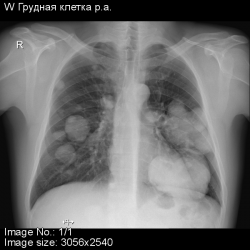

Подскажите, пожайлуста, сделал рентген, обнаруженны множественные образования в обоих легких.

Предпосылки для диагностики были затяжной кашель и температура 37,0-37,5.

На что похожа картина и локация образований?

Рада буду ошибиться. Картина метастатического поражения лёгких. Обращайтесь к онкологу. В первую очередь проверить почки и предстательную железу.

Печально,но поддержу!

Но м.б. Вегенера.

По КТ думаю, что это метастазы. В первую очередь необходимо исключить опухоль яичка (типа семиномы).

Да, на МЕТА семиномы очень похоже

Альтернативным мнение, к сожалению, может быть только по локализации.Это может быть переферическая опухоль левого легкого с МТС в оба легкие.По внешнему виду мтс первоисточник найти крайне затруднительно.Любой первоисточник опухоли может дать разные метастазы.Одни чаще при первичной конкретной опухоли, другие реже.Но мы никогда не знаем процент частоты в данном случае, поэтому определение вида и локализации первичной опухоли только по внешнему виду метастазов проводится только предположительно.Хотя в данном случае это не имеет практического значения для больного.К сожалению.